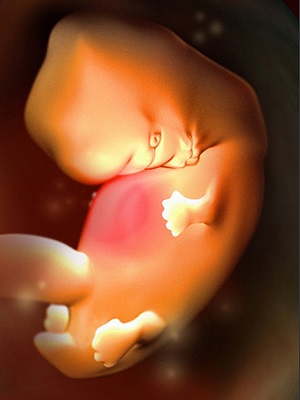

胚胎图

进入怀孕第6周后,在你的子宫里,胚胎正在迅速地成长,他(她)的心脏已经开始划分心室,并进行有规律的跳动及开始供血。这周的细胞还在迅速地分裂,主要器官包括初级的肾和心脏的雏形都已发育,神经管开始连接大脑和脊髓,原肠也开始发育。

胚胎的上面和下面开始长出肢体的幼芽,这是将来孩子的手臂和腿。日后将形成嘴巴的地方的下部,有一些小皱痕,它最终会发育成脖子和下颌。在本周面部的基本器官已经开始成形,已经能清晰地看到鼻孔,眼睛的雏形也已经具备。